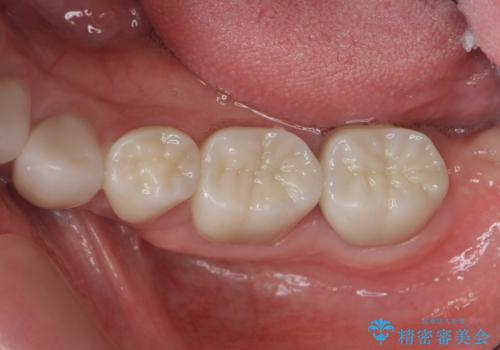

- 46.2万円(仮歯×4・フルジルコニアクラウン×4・歯周外科)費用は治療当時の料金となります

長期にわたりに安定した環境に整えることで、長く使える可能性を高めることができます。